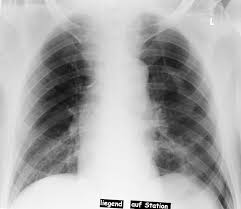

Der Raum zwischen den beiden Lungen Mediastinum ist zur Gegenseite verschoben Mediastinalverschiebung und das Zwerchfell steht auf der betroffenen Seite tiefer. Schneller Herzschlag Tachykardie Starke Schmerzen in der Brust oder Schulter. Symptome einer kollabierten Lunge aufgrund von Atelektase.

In den zu großen Blasen staut sich die Atemluft und die Ausatmung ist behindert. Die Symptome der perforierten Lunge hängen von der Menge der in die Lunge eintretenden Luft und dem Schweregrad der Perforation ab sowie davon ob eine zugrunde liegende Störung vorliegt die sie verursacht. Übersicht über die typischen Symptome Atemnot. Neben Brustschmerzen deuten normalerweise vor allem Atemnot und Atembeschwerden auf einen Lungenriss hin. Die angesammelte Luft im Pleuraraum die die Aufdehnung der Lunge behindert führt zu einer erschwerten Atmung. Eng an der Brust. Symptome einer kollabierten Lunge aufgrund von Atelektase. Dieser Kollaps kann auch Druck auf das Herz ausuben und andere Symptome verursachen. Strömt immer mehr Luft in den Pleuraraum kann sich der dadurch entstehende Überdruck auf das Herz und die umliegenden Gefäße auswirken.